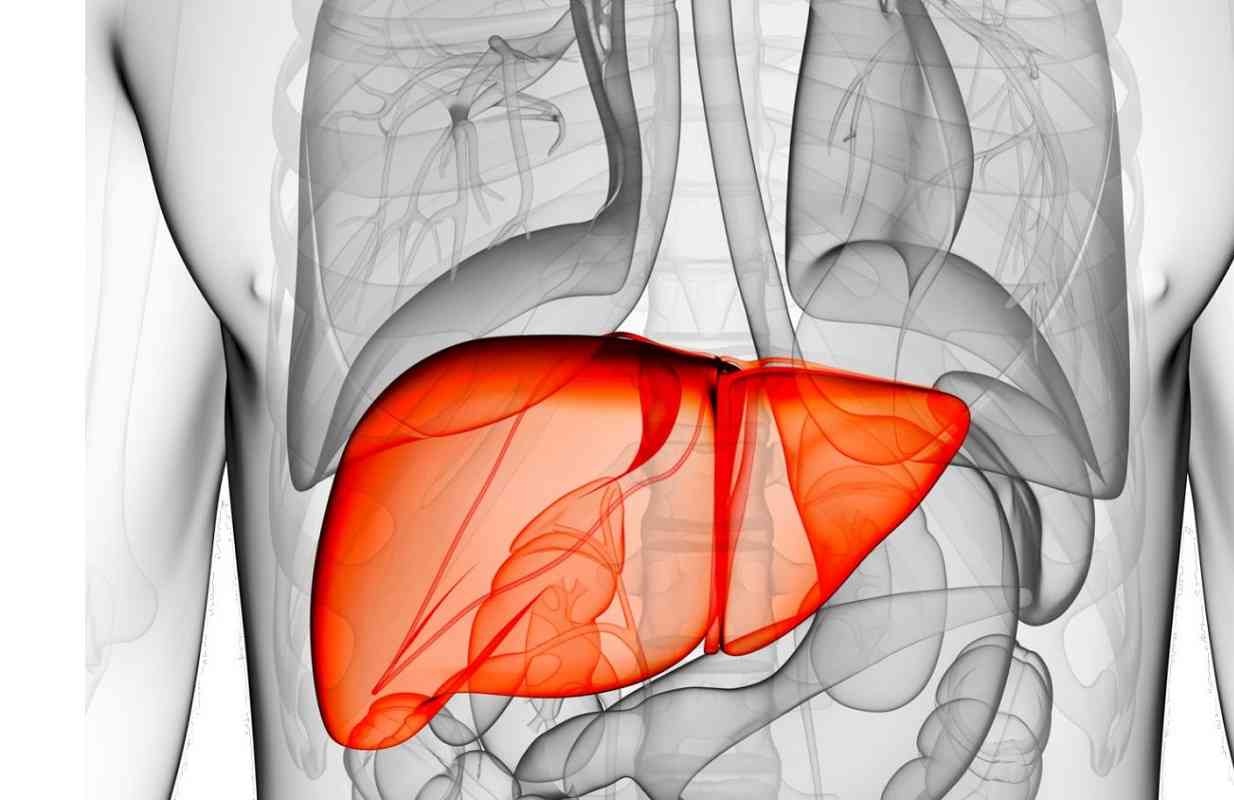

Το συκώτι είναι το δεύτερο μεγαλύτερο όργανο του σώματος. Βασική δουλειά του είναι να διώχνει τις τοξίνες από το σώμα. Επίσης, επεξεργάζεται τα θρεπτικά συστατικά από τα τρόφιμα, φιλτράρει το αίμα και μεταβολίζει τα φάρμακα που παίρνετε, αποθηκεύει γλυκογόνο, παράγει χημικές ουσίες που βοηθούν στην πήξη του αίματος, παράγει τη χολή και βοηθά στη ρύθμιση του σακχάρου στο αίμα.